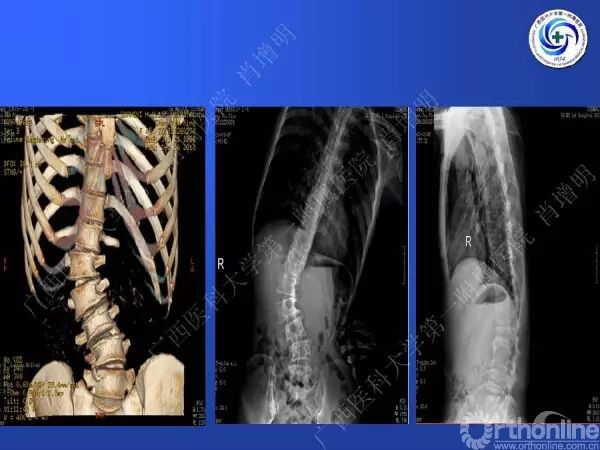

退变性脊柱侧凸是由于椎间盘退变后继发小关节退变,椎管和神经根管容积变化以及脊柱失稳,畸形等病理改变,以疼痛和神经压迫症状为主要表现的常见疾病。

退变性脊柱侧凸多发于50岁以上的中老年群体,是现代常见的老年疾病。多年来,针对该病的临床研究一直没有停步,广西医科大学第一附属医院肖增明教授细致地介绍了该病的诊疗进展。